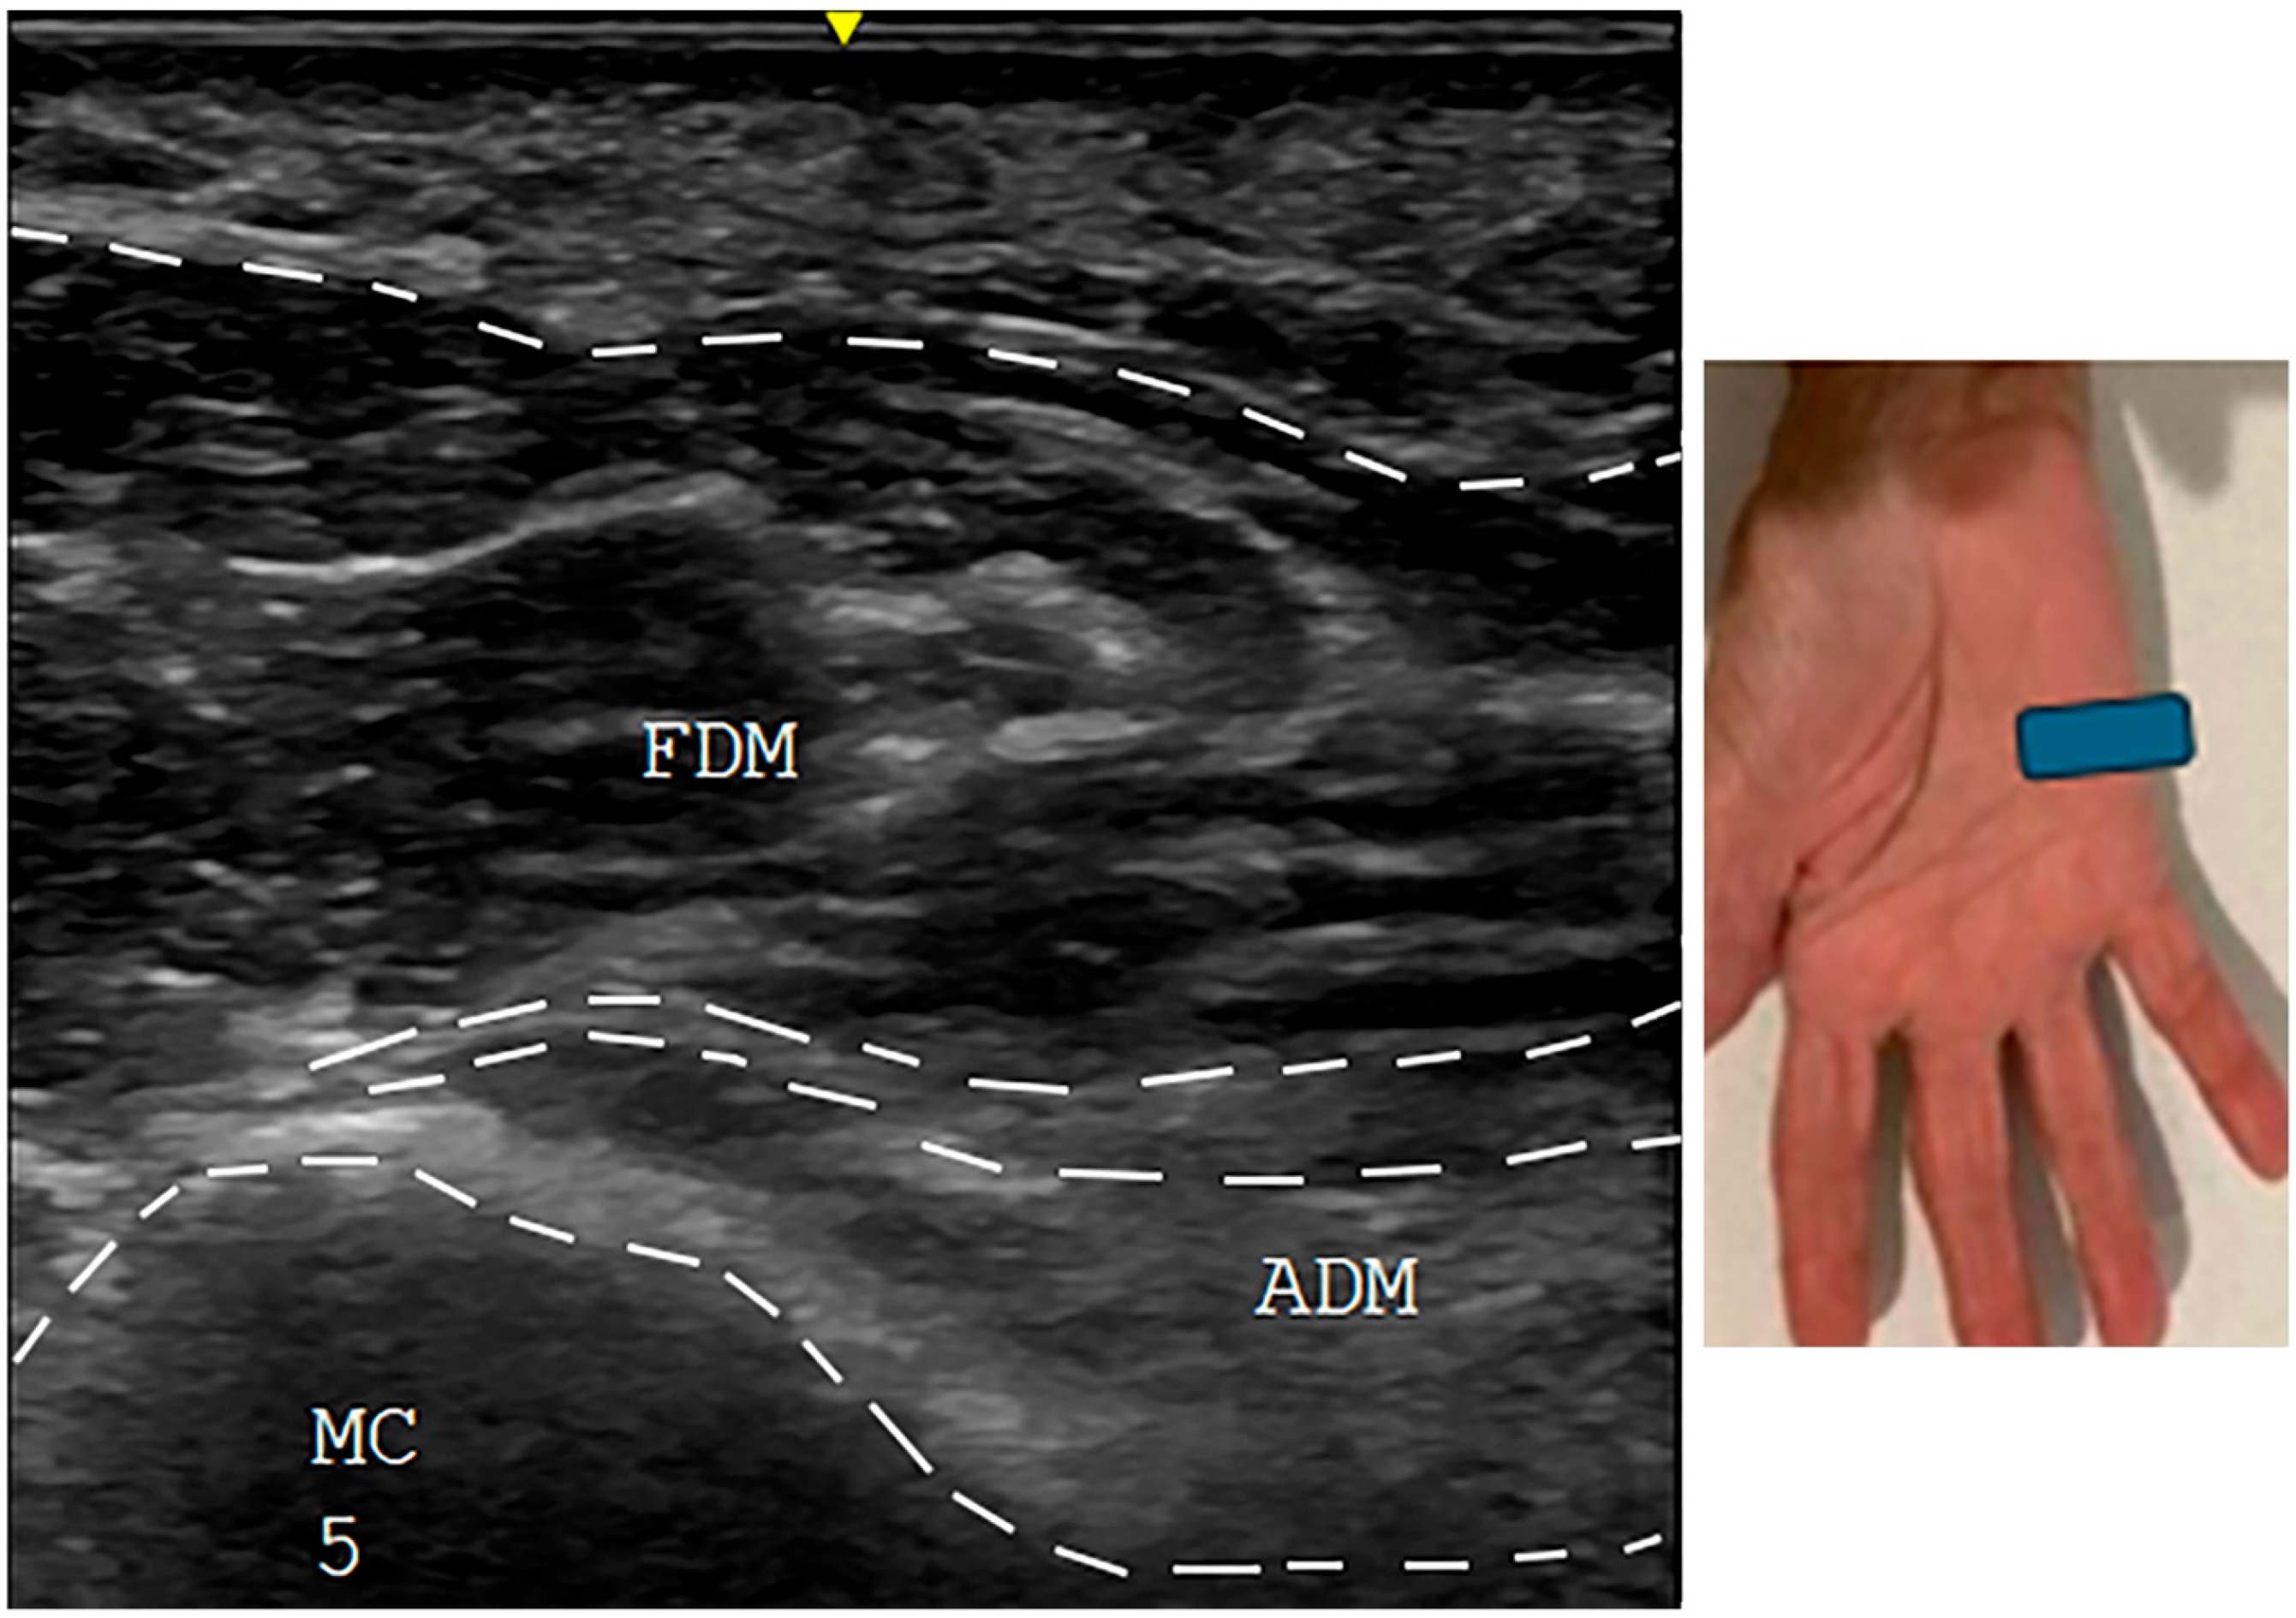

3.4. Ultrasound Studies